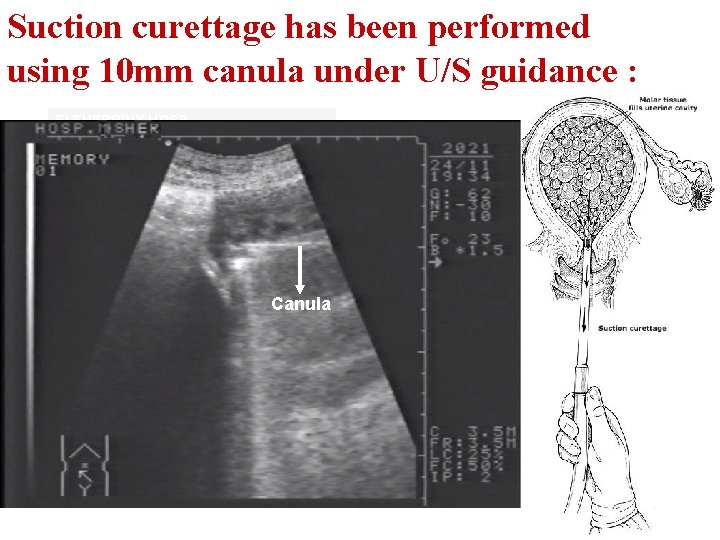

Return to Case Scenario 1 Suction curettage has been performed using 10 mm canula under U/S guidance 10 mm Canula up to a maximum of 12 mm, is usually sufficient to evacuate all complete molar pregnancies.

Suction curettage has been performed using 10 mm canula under U/S guidance : El SHERBINY HOSP Canula

U/S Guided Suction Curettage Suction curettage can be performed under U/S guidance to: Facilitate the procedure Confirm complete evacuation of contents. Garner Up. To. Date 2010